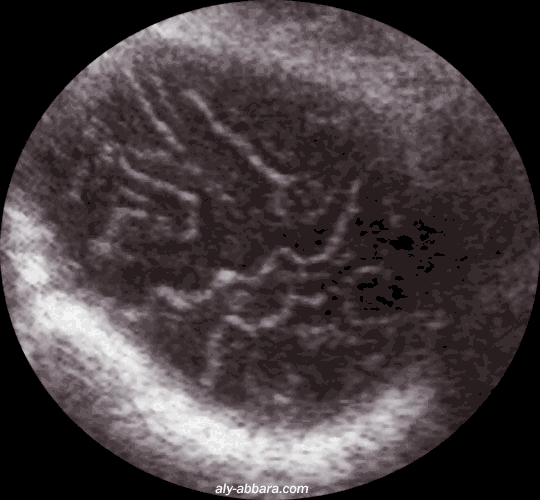

Coupe rasant la surface du cerveau fœtal à 39 SA

on met en évidence une partie des circonvolutions du cortex cérébral

A comparer à l'aspect de l'IRM fœtale des circonvolutions cérébrales